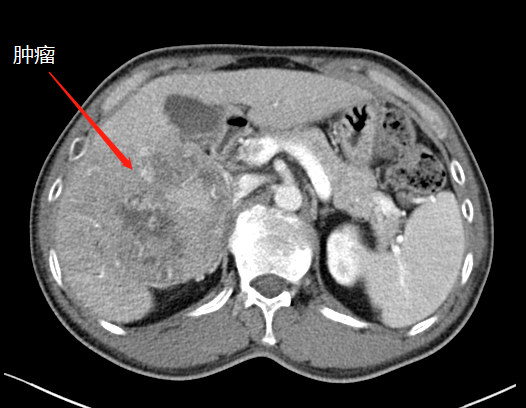

術(shù)前CT

近段時間,他因右上腹疼痛就診于瀘州市中醫(yī)醫(yī)院,在檢查中發(fā)現(xiàn)右側(cè)肝臟有一12公分左右的包塊,初步考慮為惡性腫瘤,后收治入院。通過全面檢查,診斷其為肝癌晚期,并伴有乙型肝炎、肝硬化等病癥。

“該患者入院后,通過肝臟CT,我們發(fā)現(xiàn),由于其右肝腫瘤巨大,而正常的左肝體積比較小,手術(shù)預(yù)切除肝體積達(dá)70%以上,術(shù)后殘肝體積僅28.3%,再加上該患者存在乙肝和肝硬化,剩余肝臟不足以維持他身體正常運(yùn)轉(zhuǎn)所需,不具備肝臟手術(shù)切除的基本要求?!焙鷤ケ硎?。